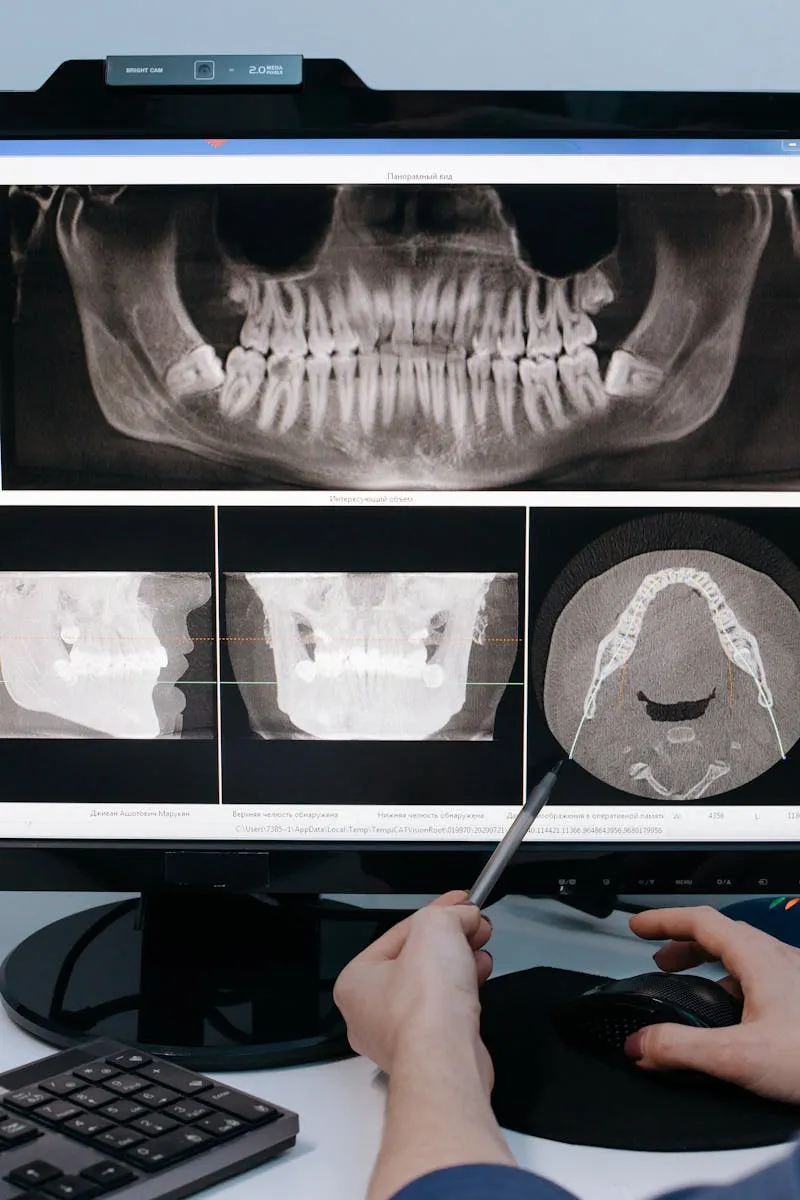

Dr. Hoang checks every filling at every visit. Not with a glance. He uses an explorer tool to probe the edges, looking for gaps where the seal between filling and tooth has broken down. Those gaps are invisible to you. They are not invisible to bacteria.